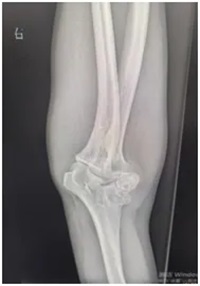

同时,刘师傅的右肘关节也出现了问题——不仅伸屈活动不灵活,外观还明显向外侧撇,正常人的肘关节本身会有一点生理性外翻(女性约10~15°,男性约5~10°左右),可医生测量后发现,刘师傅的肘关节外翻角度竟然达到了30°左右,远远超出了正常范围!

X线显示:肘关节存在明显畸形改变;